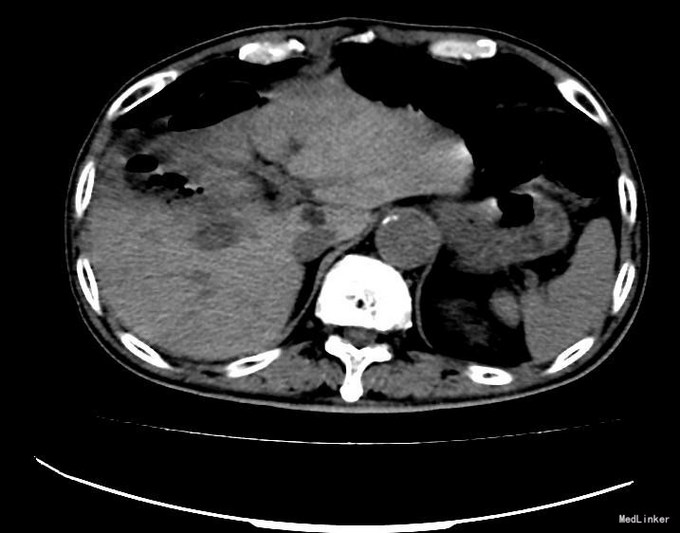

查体:右上腹轻压痛,无反跳痛、肌紧张。墨菲氏征弱阳性。 辅助检查:腹部CT:胆囊体积增大,壁增厚,以胆囊底部为著,增强扫描可见轻度强化,胆囊周围可见积液。MRI:胆囊增大,壁增厚,壁内可见多发结节状低信号灶。胆囊内可见泥沙样短T2信号影。

术前诊断:胆囊占位性病变; 术后诊断:胆囊结石胆囊炎; 治疗:剖腹探查、胆囊及部分肝脏切除术(术中发现胆囊约9x6×4cm,张力高,浆膜增厚,呈炎症水肿表现,胆囊底部与肝脏分界不清。决定行胆囊及部分肝脏(胆囊床)切除术。解剖胆囊三角,分别游离并处理胆囊管、胆囊动脉,予以丝线结扎。将距胆囊2cm的肝脏组织连同胆囊完整切除,期间阻断肝门5次,3-10分钟不等,距离胆总管0.5cm将胆囊管切断,移出胆囊。送冰冻病理,提示符合胆囊炎性表现。)